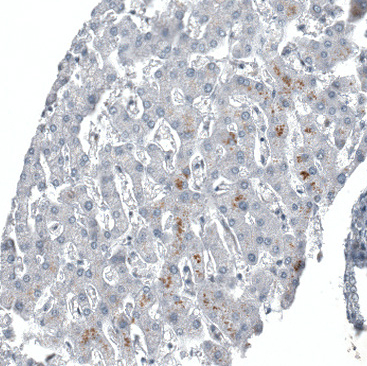

Immunohistochemical staining of human testis shows moderate nuclear positivity in cells in seminiferous ducts.